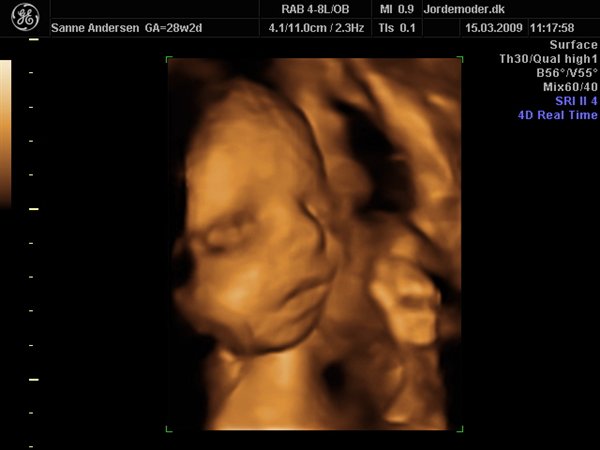

Her er Stellas nye Lillebror 27+3:

Til venstre ses lillesøster (Celina) i uge 27+3